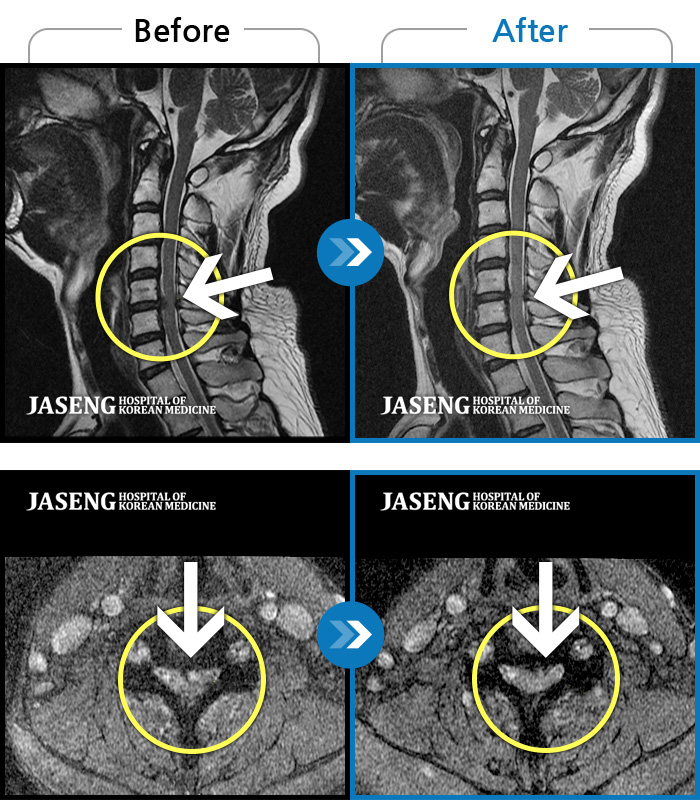

MRI 치료사례

교통사고로 인해 기존의 퇴행성 디스크가 파열되어 극심한 경추의 통증과 손의 힘 빠짐, 손가락의 저림 증상을 호소하였음